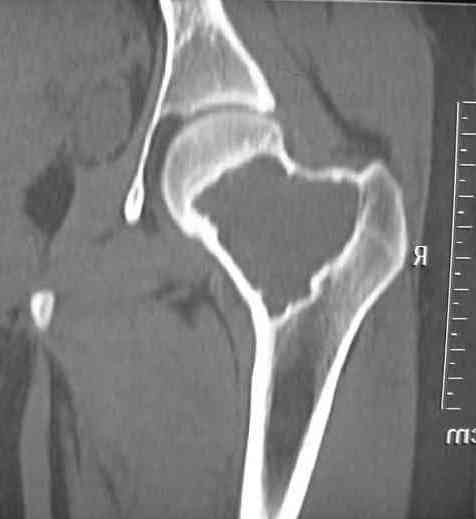

Больная Л.,   23 года.

Из анамнеза:со слов больной в 2006 г. появились боли правой н/конечности, обратилась поместу жительства к хирургу, было выполнена МРТ поясничного отдела позвоночника,назначено физиолечение. Через 2 месяца боли прекратились, через 4 месяца рецидивболевого синдрома. С 2006 – 2010 проводилось консервативное лечение по поводуостеохондроза поясничного отдела позвоночника. В октябре 2010 г. боли усилились.Выполнены Ro и КТправого тазобедренного сустава, выявлен очаг патологической перестройки. Быланаправлена на консультацию в УНИИТО.

В УНИИТО виюне 2011 г. поставлен дифференциальный диагноз между фибромой, солитарной костнойкистой и гигантоклеточной опухолью.